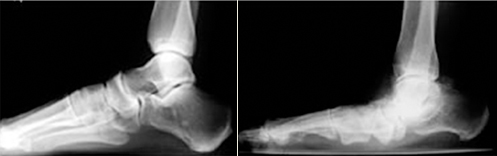

평발이란 발의 모양을 이루는 종아치가 내려앉아서 족저부가 편평하게 되는 변형이며 주로 소아에서 발생하지만 어른에게서도 발생할 수 있습니다.

평발은 유연성 평편족과 강직성 평편족으로 분류되며 유연성 편평족은 대부분 소아에서는 증상이 없으며 12-14세가 지나서 통증을 호소 하는 경우가 많습니다. 어른이 될 때까지 남아있는 경우도 있으나 대부분 증상은 경미한 편 입니다.